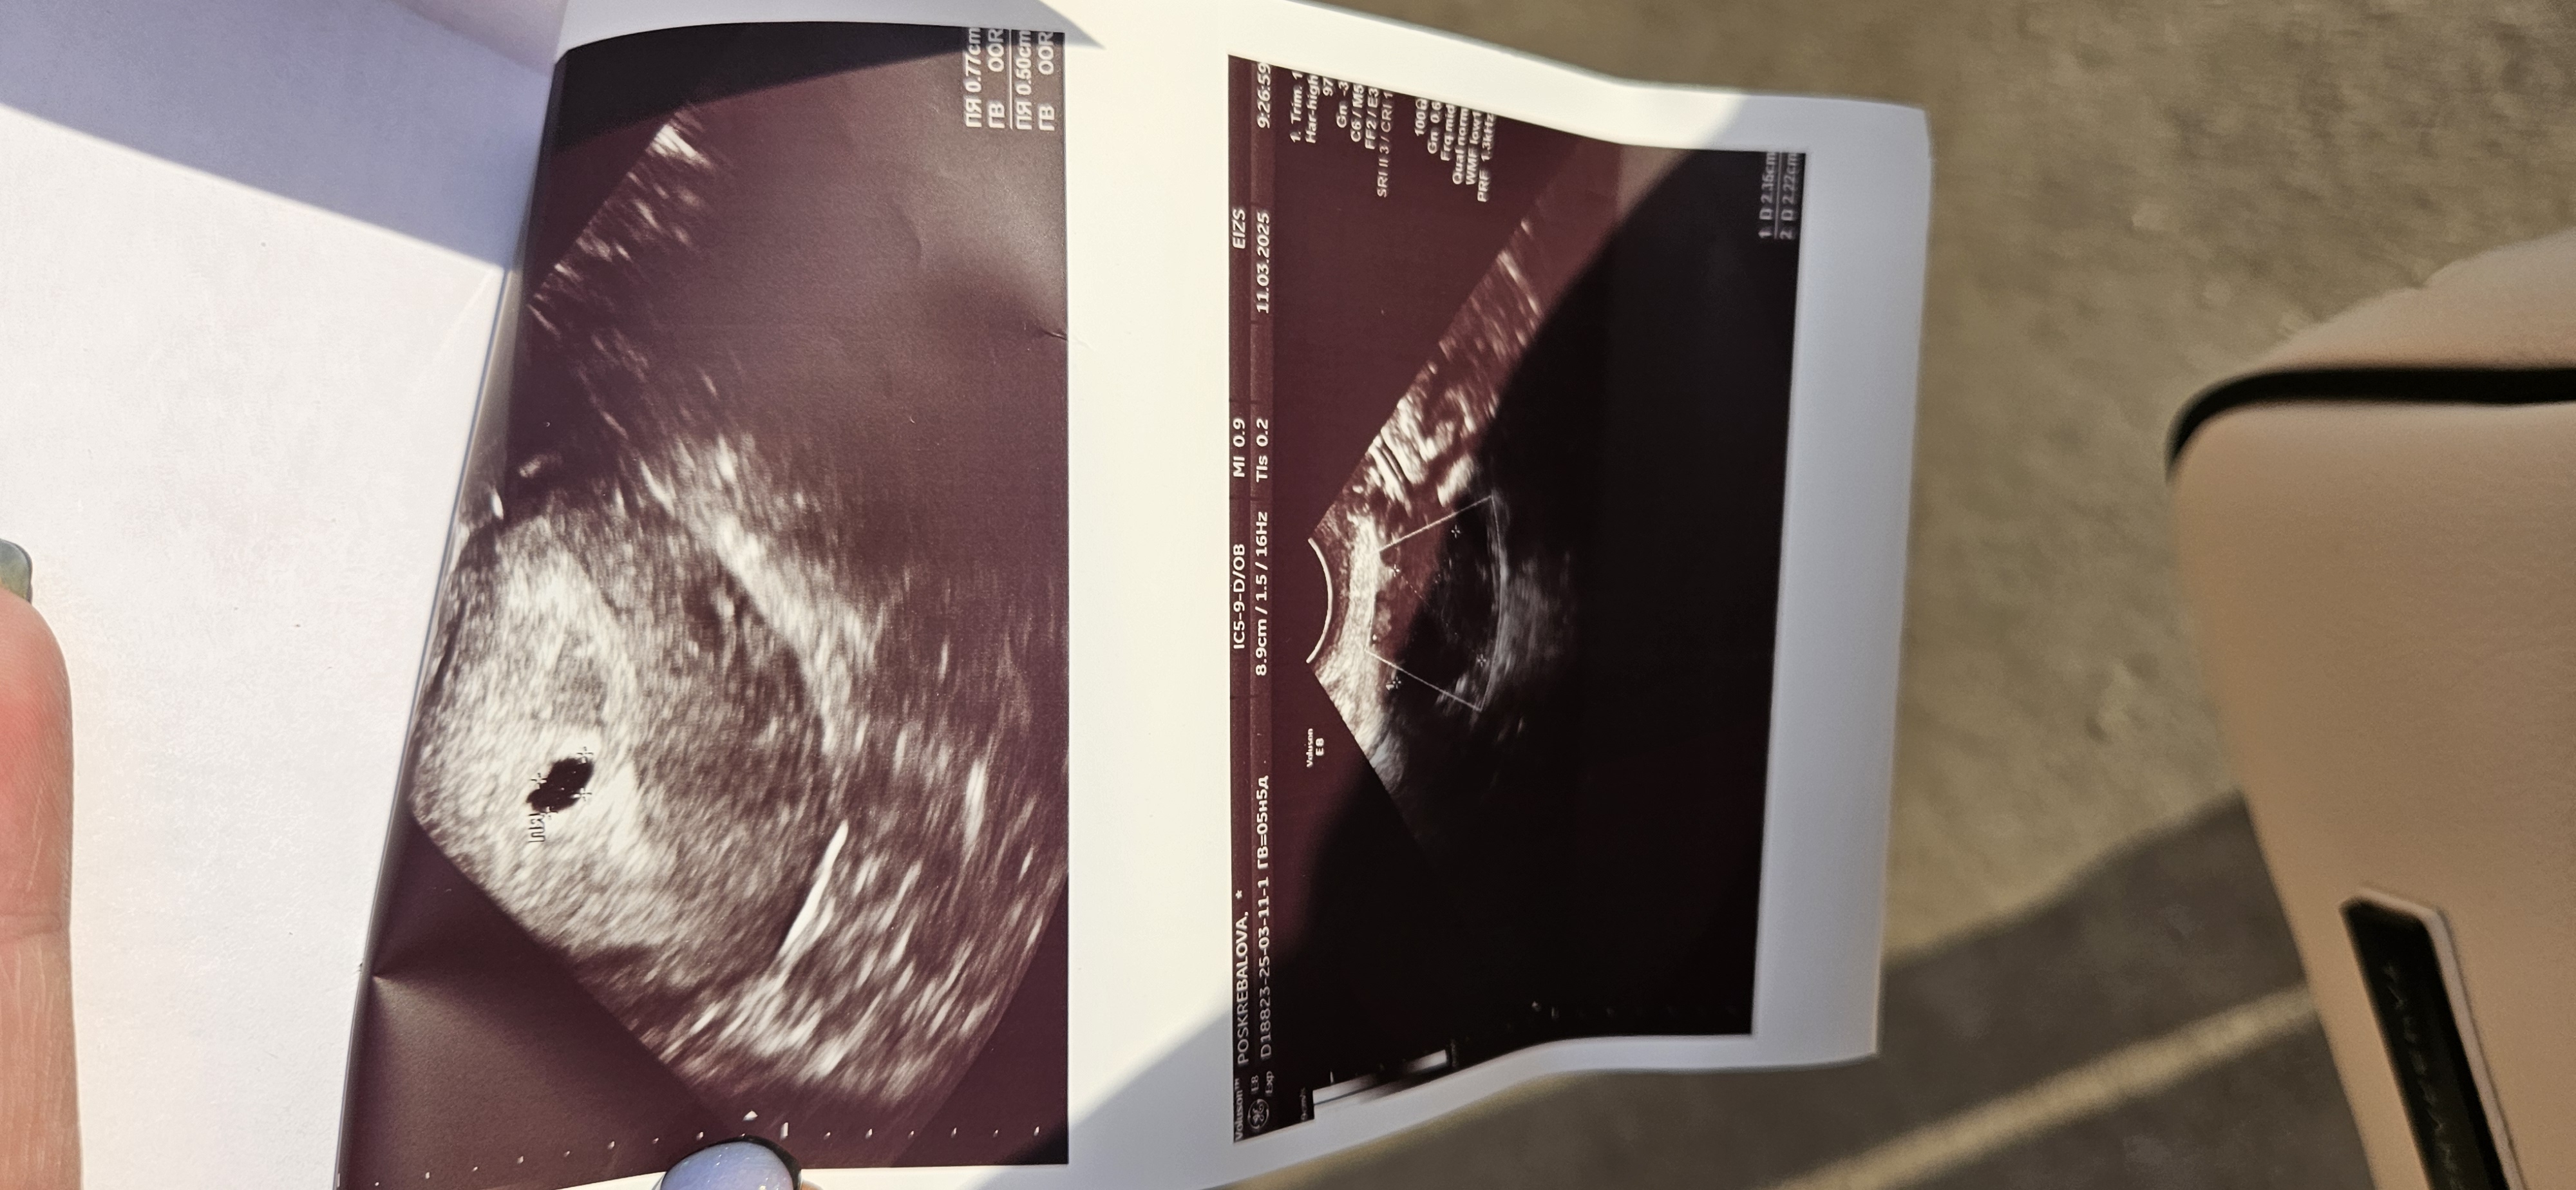

Поделитесь своими показателями)месячные были 30.01,овуляция по тестам 16.02 ,па тоже 16.02.делала тест 24.02 был кристально чист)1 марта сделала ещё раз тест и там уже были не яркие полоски .хгч сдавала

02.03 115

4.03 310

06.03 836.

Сегодня не выдержала и сходила на узи,по месячным 5н5д увидели пя.все ли хорошо?или я себя накручиваю?выделения прозрачные,иногда тянет левый бок